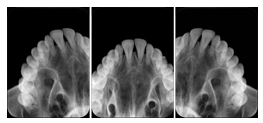

3. A dental provider wishes to capture a series of DICOM IO images for the patient’s dentition. The tooth morphology, teeth are divided into molars, premolars, canines and incisors, and a number of images for each jaw. The anatomic information was captured utilizing the triplet of schema. This standard code sequence is based on ISO 3950-2010, Dentistry - Designation system for teeth and areas of the oral cavity.

Every IO image should have anatomic information either through the primary or modifier sequence.

In most standard cases, images are oriented in structured layouts. These structured displays are useful to be shared between providers for reference purposes.